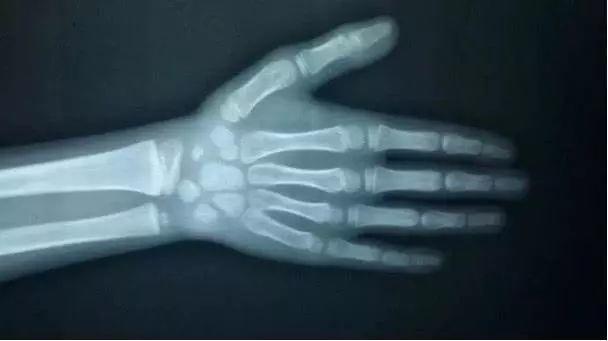

怎么看骨龄图片_怎么看骨龄图片